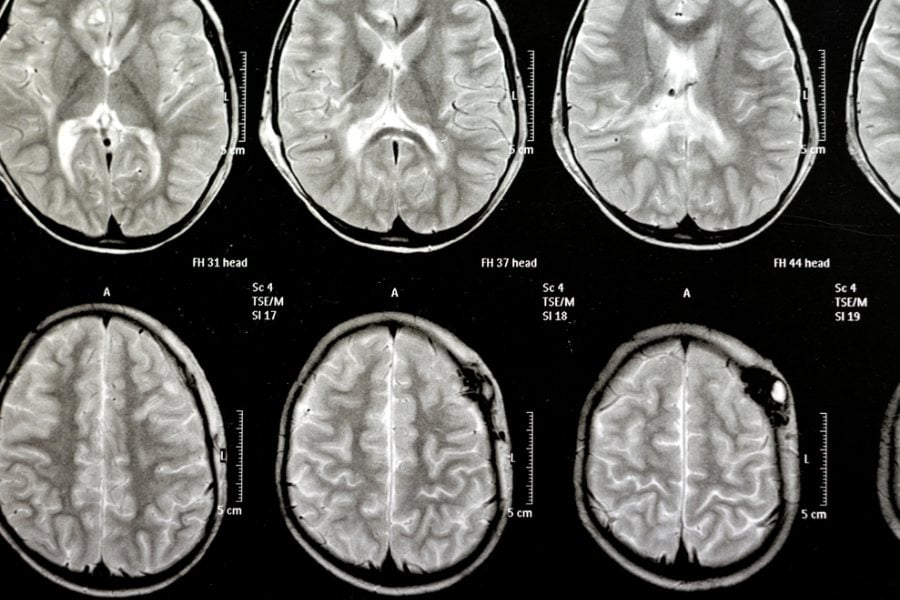

Самият термин произлиза от гръцките думи „хидро“ (в превод: вода) и „цефалус“ (в превод: глава). Водата всъщност е гръбначно-мозъчна/цереброспинална течност, която нормално се съдържа във вентрикулите и играе важна роля за защита, подхранване и изчистване на отпадните вещества от мозъка и гръбначния стълб. При хидроцефалия този баланс е нарушен и това причинява натрупване на течността и натиск върху мозъка.

По-малко позната и специфична форма на заболяването е нормотензивната хидроцефалия. Тя обикновено засяга възрастни над 60 години и се характеризира с нормално налягане на цереброспиналната течност, но разширени вентрикули. Симптомите включват:

Хидроцефалия е медицинско състояние, при което се натрупва излишна гръбначно-мозъчна течност (ликвор) в мозъка, по-специално в пространствата, наречени вентрикули.